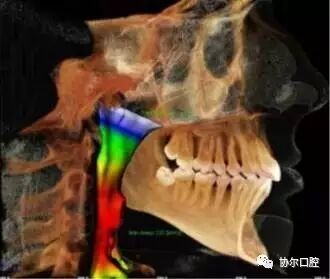

精确的气道分析

一句话,使用KaVo 3D eXam i独有的软件可以准确而高效地实现对种植、基台、修复体的设计,帮助种植、修复、牙体牙髓以及正畸计划的制定和实施。完整的骨结构TMJ分析,精确的气道分析是很多三合一CBCT达不到的,也是医生在诊断中容易忽视的。工欲善其事,必先利其器,好的影像学检查资料,将为医生的治疗锦上添花。